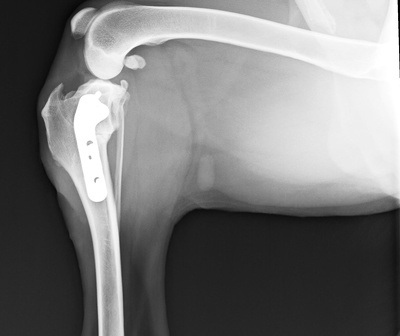

整形外科

藤井寺動物病院 院長

藤井寺動物病院・動物人工関節センター 院長、博士(獣医学)